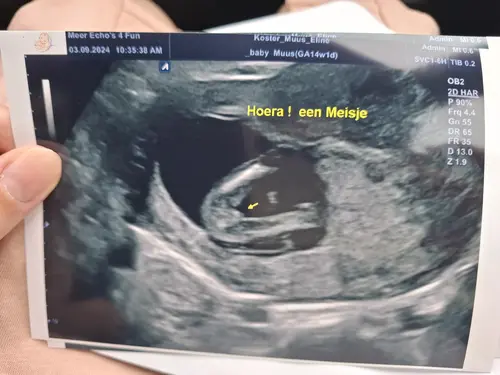

Super leuk dit onderwerp, ik heb 24 september de geslacht echo staan als ze willen meewerken.

Ik ben zwanger van een tweeling, dus ik ben erg benieuwd. Mijn zoontje wordt ineens grote broer van twee🥰

Zo leuk dat jullie dadelijk een jongen en een meisje hebben.☺️🩵❤️